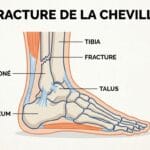

Lorsque la douleur ne reste pas localisée à la cheville mais progresse vers le mollet, le tibia ou même la cuisse, cela évoque un problème plus profond. Plusieurs mécanismes peuvent être en cause :

Causes neurologiques : canal tarsien, sciatique, nerfs périphériques

- Le nerf tibial postérieur peut être comprimé au niveau de la cheville (syndrome du canal tarsien).

- Cela provoque des douleurs irradiantes vers la voûte plantaire ou le mollet.

- Les sciatiques atypiques (par compression basse) peuvent aussi donner des douleurs cheville-jambe.

IRM ou scanner

- Permet de visualiser les lésions osseuses, nerveuses ou ligamentaires invisibles à la radio.

- L’IRM est l’examen de choix en cas de doute sur une tendinopathie complexe ou une atteinte nerveuse.